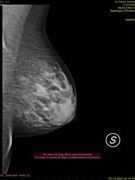

Parenchimi fibroghiandari con componente adiposo nei quali l'esame ecografico integrato da esame mammografico non ha evidenziato aspetti patologici,anche nell'area di maggiore densità parenchimale nel q superiore est di sn. Si consiglia un controllo ecografico fra 6 mesi salvo diversa indicazione clinica.

Queste sono le.immagini della mammografia,e ricordo sempre il motivo oer la quale ho fatto tutti questi accertamenti,presenza di un nodulo o pallina seno sinistro,chr a quanto pare rivelatasi mia conformazione del seno. (Come già da lei ribadito)